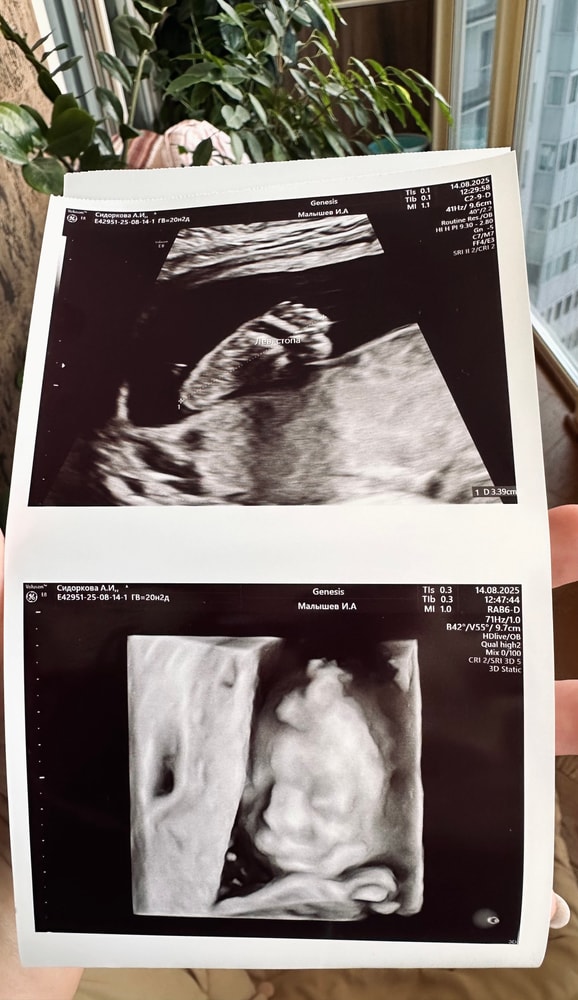

У нас будет третья дочка!)))

Третья кукла по узи 333г)) даже интересно!

ПДР на Новый год 🎄